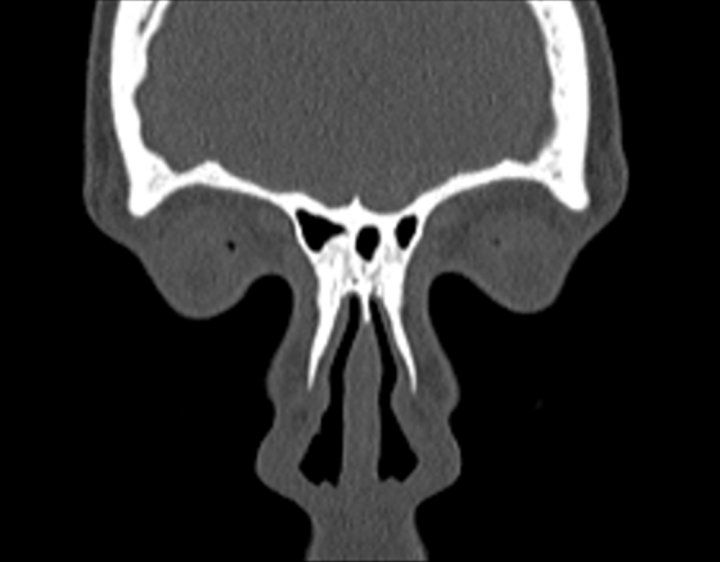

Click any image for labels.